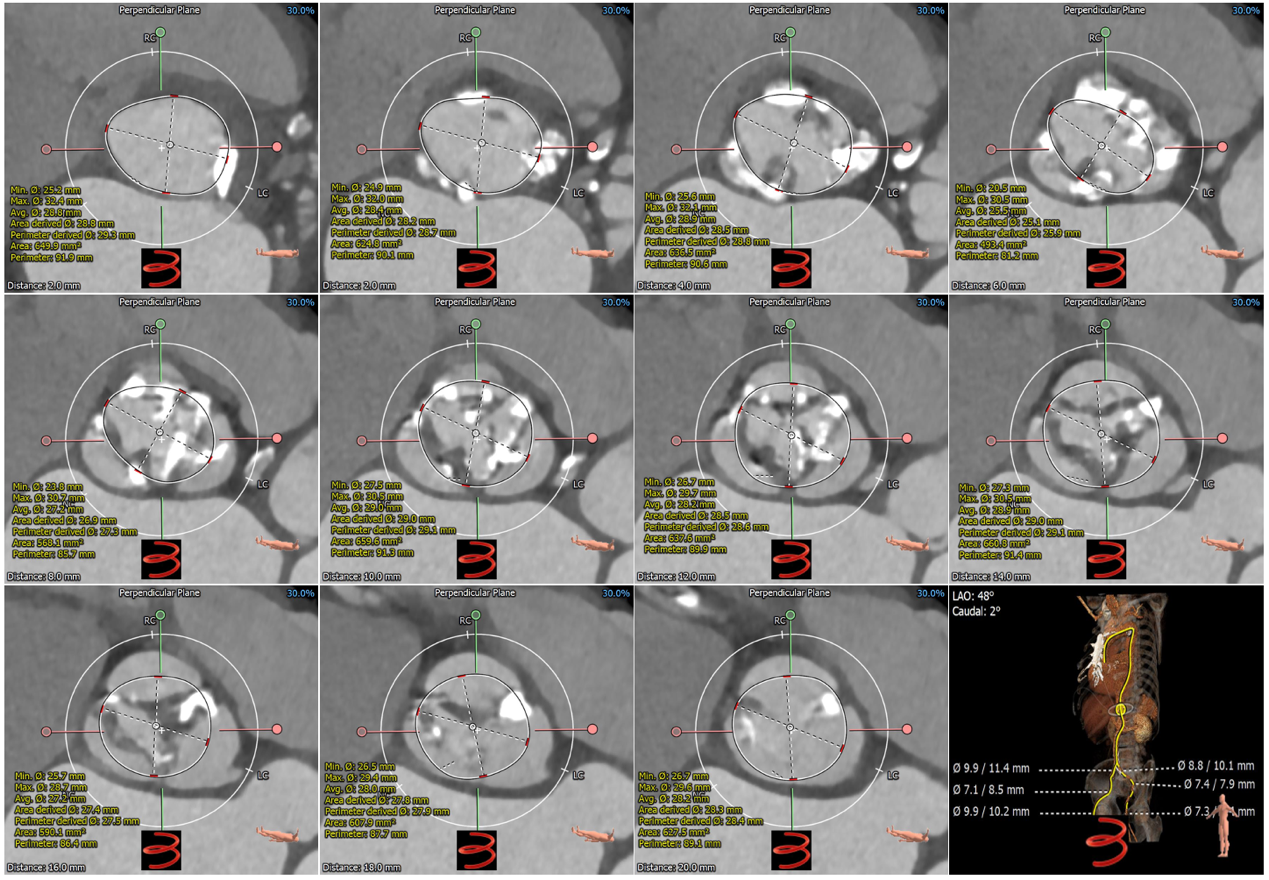

患者男,82岁,主诉:活动后胸闷加重2月,于2021年4月30日入阜外医院。患者近2个月来胸闷、气促,与活动有关,多于行走时、上楼时及情绪变化时出现,每次持续约数分钟后可缓解。体格检查:体温36.0℃,脉搏85次/min,呼吸12次/分,血压88/52 mmHg(1 mmHg=0.133 kPa)。双肺呼吸音清,未闻及干湿性啰音;心率85次/分,律齐,主动脉瓣听诊区可闻及3/6 级喷射性杂音;双下肢无水肿。入院诊断: 主动脉瓣重度狭窄、三尖瓣重度关闭不全、冠状动脉粥样硬化性心脏病、NYHA心功能Ⅲ级、高脂血症、肺动脉高压。入院心电图为窦性心律,ST-T改变。超声心动图:主动脉瓣瓣口面积为0.38 m2,瓣口峰值流速5.0 m/s,平均跨瓣压差66 mmHg,左室舒张末径48 mm,左室射血分数45%,三尖瓣大量反流,肺动脉压力57 mmHg。实验室检查:白细胞计数4.67×109 /L,血红蛋白144 g/L,血小板计数180×109 /L,血肌酐104.96 umol/L,钾离子4.55 mmol/L,NT-ProBNP 5987 pg/ml。冠脉CT评估冠脉三支未见明显狭窄。3Mensio软件评估主动脉根部解剖:功能性二叶瓣,左右融合,融合区团块状钙化;三个瓣叶钙化均匀,左冠瓣钙化延伸至左室流出道;三个瓣叶增厚,呈风湿样改变;冠脉开口高度可(L:13.8 mm,R:22.2 mm),左冠开口水平可见明显瓣叶结构,且左冠瓣叶明显增厚钙化,考虑到左右融合区存在团块状钙化,不易被植入的瓣膜扩张开,因此冠脉闭塞风险不大,注意术中球囊预扩张进一步明确冠脉闭塞风险;瓣环长短径分别为24.8*32.6 mm,周长为90.1 mm,面积为624.2 mm2;其他测量参数见图1,多平面测量参数及全主动脉评估见图2。患者高龄,拒绝外科手术,外科手术风险STS评分为2.891 %;主动脉瓣膜解剖上适合行TAVR;纠正重度主动脉瓣狭窄后的预期寿命超过1 年,符合TAVR适应证,无手术禁忌证,因此决定行TAVR。

图1患者主动脉根部CT评估

A:瓣环;B:左心室流出道;C:瓦氏窦;D:左侧冠脉开口高度;E:窦管结合部 F:升主动脉(最宽处);G:虚拟瓣叶形态及钙化分布;H:右侧冠脉开口高度。

图2患者CT多平面测量及全主动脉评估

A,B,C,D,E,F, G, H, I, J, K分别为瓣环下2mm和瓣环上的2,4,6,8,10,12,14,16,18mm水平,测量圆圈为术前推测植入瓣架展开的最大形态;L:全主动脉CT三维重建显示血管无明显狭窄。